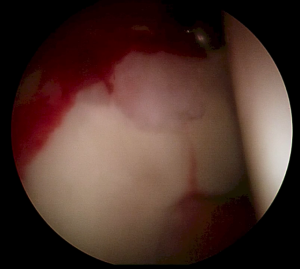

El propósito del estudio es la evaluación clínica del manejo capsular con tratamiento artroscópico del pinzamiento femoroacetabular y desgarros del labrum mediante la comparación de los resultados funcionales de la cápsula cerrada frente a la abierta.

Artículo Internacional